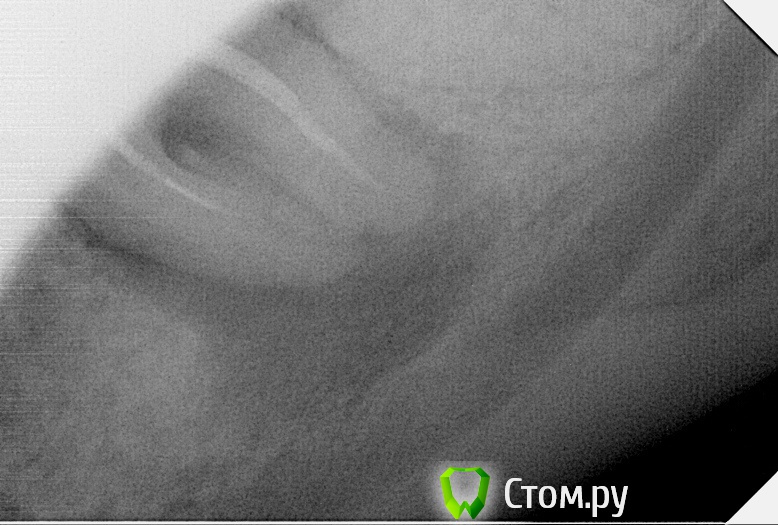

SanderS Опубликовано 28 октября, 2014 Поделиться Опубликовано 28 октября, 2014 (изменено) Пришла пациентка, жалобы на периодически ноющие боли слева НЧ, немного подвижен мост 3.7-3.8. Прогноз? Мосту 4 года, кармана по медиальной стенке не нащупал Изменено 28 октября, 2014 пользователем SanderS Ссылка на комментарий